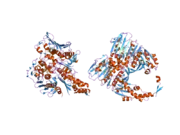

DNA topoisomerase IIα is a human enzyme encoded by the TOP2A gene.

Topoisomerase IIα relieves topological DNA stress during transcription, condenses chromosomes, and separates chromatids. It catalyzes the transient breaking and rejoining of two strands of duplex DNA which allows the strands to pass through one another. Two forms of this enzyme exist as likely products of a gene duplication event. The gene encoding this form, alpha, is localized to chromosome 17 and the beta gene is localized to chromosome 3. The gene encoding this enzyme functions as the target for several chemotherapy agents[5] and a variety of mutations in this gene have been associated with the development of drug resistance. Reduced activity of this enzyme may also play a role in ataxia-telangiectasia.[6]